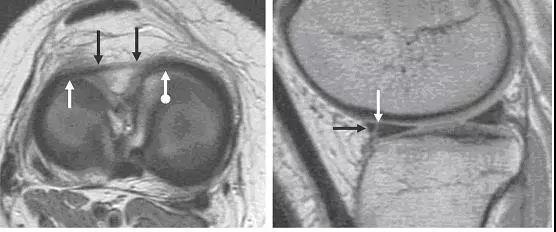

图 14 半月板根部撕裂和半月板膨出

左图:冠状面可见内侧半月板后角在与根部(与胫骨连接的部位,白色大箭头)交接的部位有一个全层的撕裂(白色小箭头),可与对侧正常结构对比(黑色箭头)。右图:冠状面可见内侧半月板体部膨出关节(白色箭头),半跨与胫骨平台上。本图还可看到内侧股骨髁的关节软骨有相较于外侧的退行性缺失。